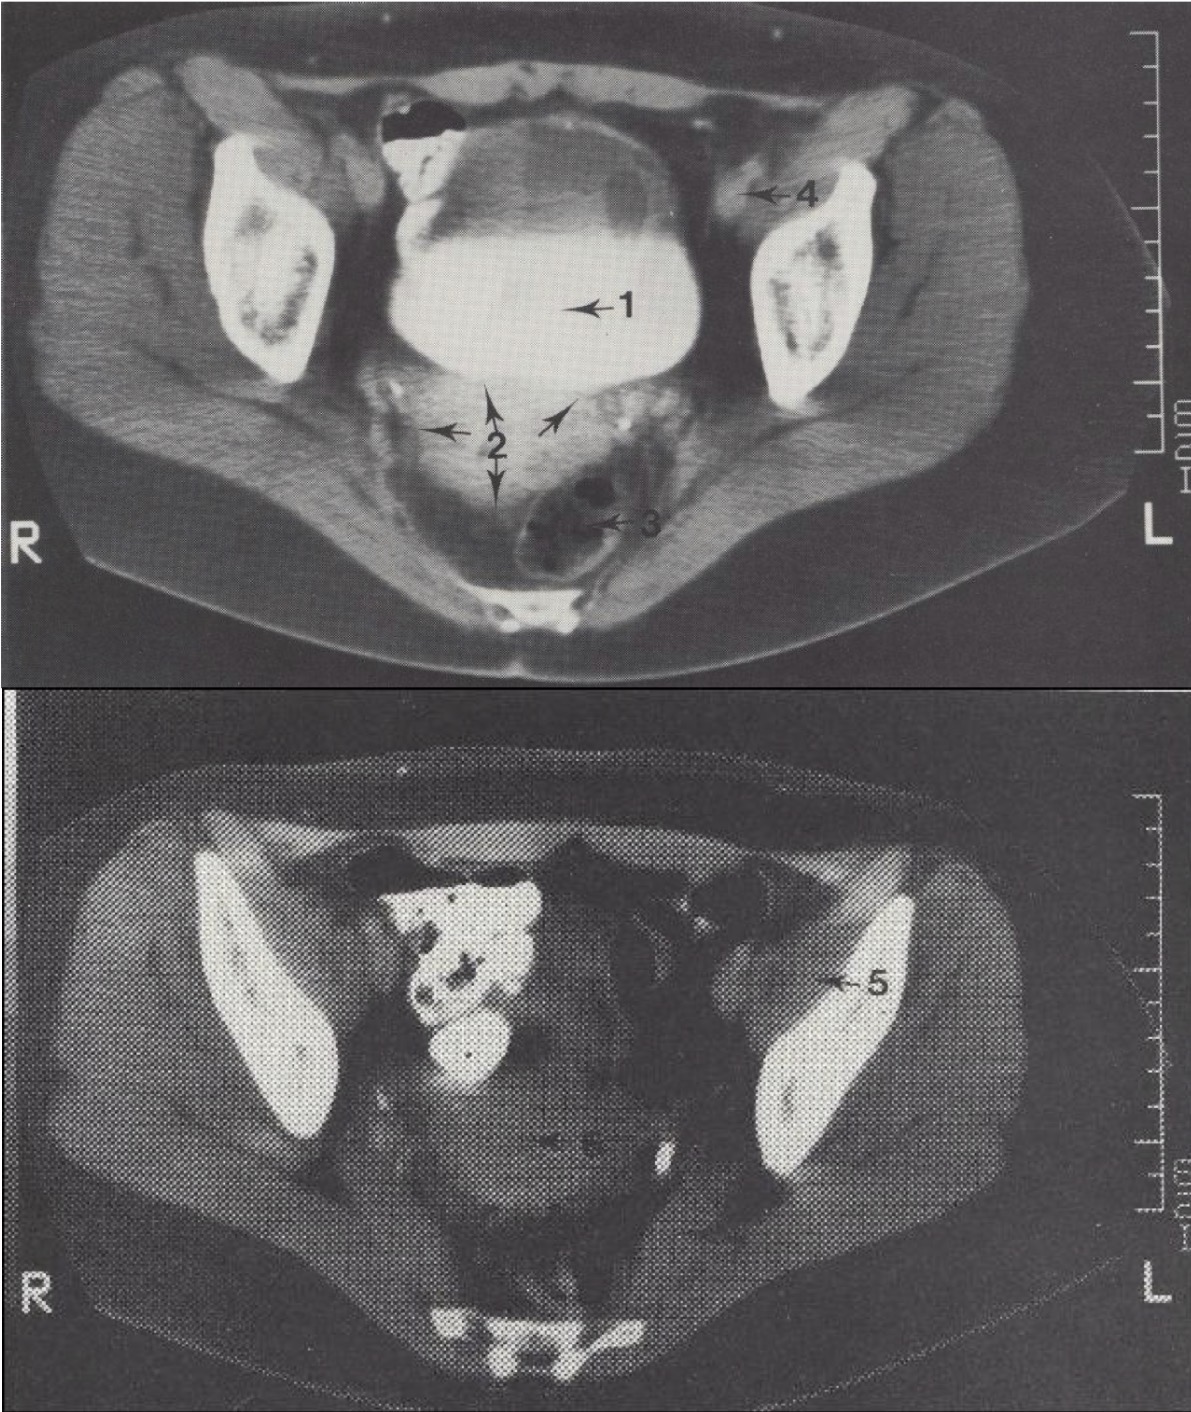

5

M. iliopsoas (klubinis juosmens raumuo)

Metodika

KT pjūviai atlikti virš acetabulum (gūžduobės). Naudotas intraveninis kontrastas (šlapimo takams) ir peroralinis kontrastas (žarnyno kilpoms).

Topografija

Gimdos šešėlis (corpus uteri) matomas tarp tiesiosios žarnos (rectum) ir šlapimo pūslės (vesica urinaria).